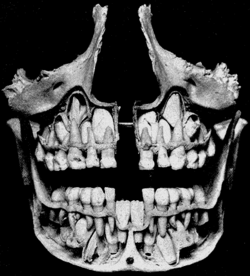

![]() This cut view of a child's skull shows permanent teeth located above and below the deciduous teeth prior to exfoliation. The deciduous mandibular central incisors have already been exfoliated (Gray's Anatomy) | |